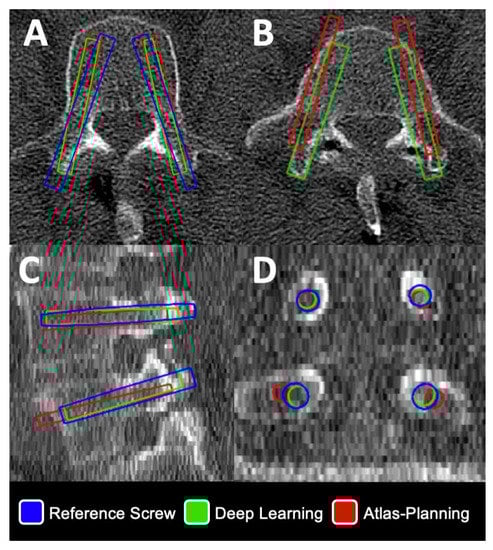

2.4. Automatic Planning by Self-Derived Approach Based on Deep Learning

2.5. Automatic Planning by a Commercial Atlas-Based Approach